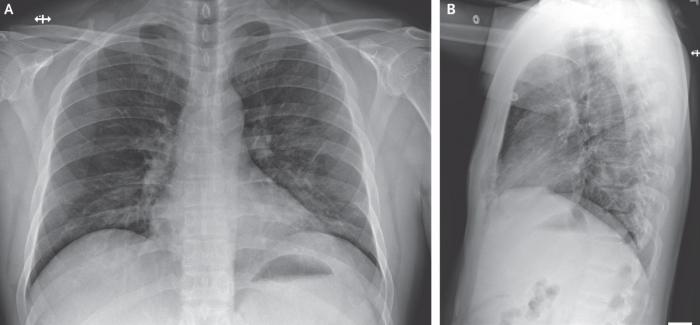

住院第8天(患病第12天),也就是注射瑞德西韦后第二天,患者的临床状况得到明确改善。停止吸氧,在不吸氧的情况下,血氧饱和度值提高到94%至96%。先前的双侧下叶罗音消失。食欲得到改善,除了间歇性干咳和鼻涕外,没有其他症状。截至2020年1月30日,患者仍在住院治疗。他没有发热,除咳嗽外,所有症状均已缓解,咳嗽的程度正在减轻。